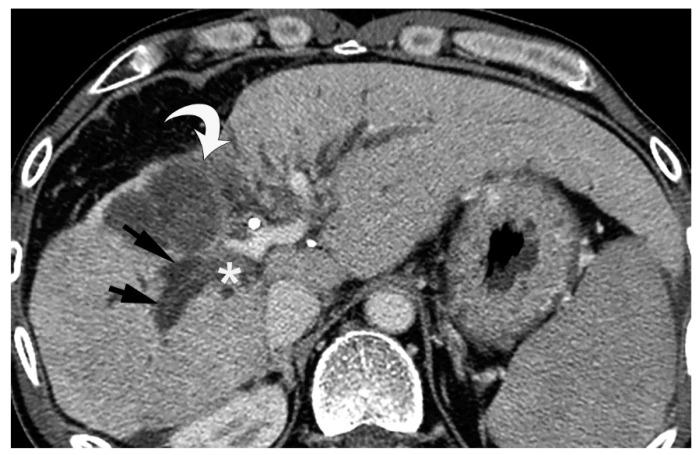

Bile duct necrosis (BDN) with biloma formation is a type of ischemic bile duct injury that is one of the serious complications associated with transarterial therapies, such as transcatheter chemoembolization therapy (TACE), and radioembolization for hepatocellular carcinoma (HCC) and hepatic arterial infusion chemotherapy (HAIC) for metastatic liver cancer from colorectal carcinoma. In terms of the occurrence of BDN and subsequent biloma formation, ischemic injury to the peribiliary vascular plexus (PBP), the supporting vessel of bile duct epithelium, is thought to be intimately associated. In this paper, we first describe the anatomy, blood supply, and function of the intrahepatic bile duct, and then illustrate the pathophysiology of BDN, and finally present the imaging findings of BDN. Under the process of BDN formation, ischemia of the PBP induces the disruption of the bile duct epithelial protection mechanism that causes coagulation and fibrinoid necrosis of the surrounding tissue by the detergent action of exuded bile acids, and eventually a biloma forms. Once BDN occurs, persistent tissue damage to the surrounding bile duct is induced by imbibed bile acids, and portal vein thrombosis may also be observed. On pre-contrast and contrast-enhanced computed tomography (CT), BDN shows similar findings to intrahepatic bile duct dilatation, and, therefore, it is sometimes misdiagnosed. Differentiation of imaging findings on CT and ultrasound (US)/magnetic resonance (MR) imaging/MR cholangiopancreatography (MRCP) is important for correct diagnosis of BDN.

伴有胆汁瘤形成的胆管坏死(BDN)是一种缺血性胆管损伤,是经动脉治疗相关的严重并发症之一,如经导管肝动脉化疗栓塞术(TACE)、肝细胞癌(HCC)的放射性栓塞以及结直肠癌肝转移的肝动脉灌注化疗(HAIC)。就BDN的发生及随后胆汁瘤的形成而言,胆管周围血管丛(PBP)(胆管上皮的支持血管)的缺血性损伤被认为与之密切相关。在本文中,我们首先描述肝内胆管的解剖结构、血液供应和功能,然后阐述BDN的病理生理学,最后介绍BDN的影像学表现。在BDN形成过程中,PBP的缺血会导致胆管上皮保护机制的破坏,渗出的胆汁酸通过去污剂作用导致周围组织发生凝固性坏死和纤维蛋白样坏死,最终形成胆汁瘤。一旦发生BDN,吸收的胆汁酸会导致周围胆管持续的组织损伤,还可能观察到门静脉血栓形成。在平扫及增强计算机断层扫描(CT)上,BDN表现与肝内胆管扩张相似,因此有时会被误诊。CT及超声(US)/磁共振(MR)成像/磁共振胰胆管造影(MRCP)上影像学表现的鉴别对于BDN的正确诊断很重要。